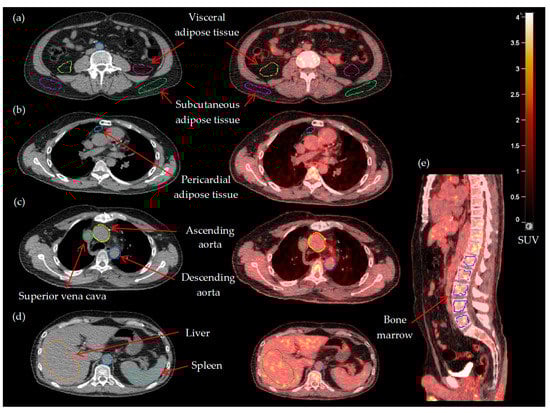

| Entire aorta (TBRmax) | 2.27 ± 0.39 |

| Visceral adipose tissue (TBRmean) | 0.17 (0.15–0.21) |

| Subcutaneous adipose tissue (TBRmean) | 0.13 (0.11–0.16) |

| Pericardial adipose tissue (TBRmean) | 0.34 (0.26–0.52) |

| Spleen (SLRmean) | 0.94 ± 0.10 |

| Bone marrow (BLRmean) | 1.00 ± 0.20 |